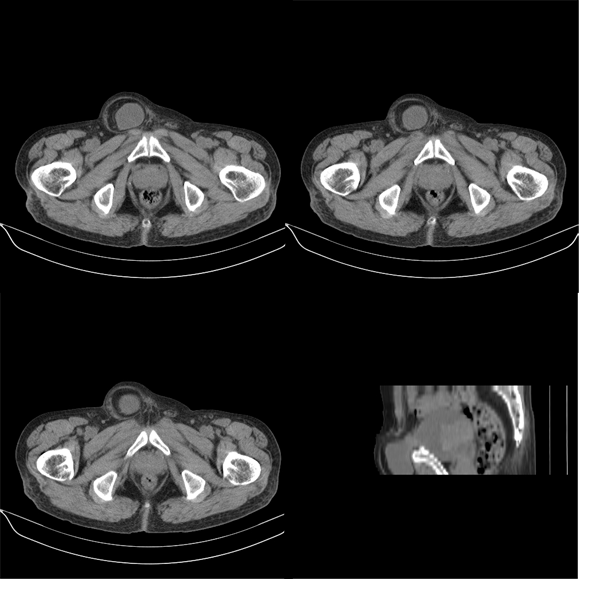

m79y自述30年前做过疝手术,20年前间断出现尿血,每次经抗炎治疗后即好转,近一月来又出现尿血但抗炎后仍尿血.现做双肾+盆腔ct:

双肾10mm扫描

盆腔5mmct扫描

该病人年龄过大故放弃了增强.ct做完后本人检查病人发现病人耻骨联合上稍偏右见一突出的包块影,质地柔软,平卧位手压后可以回缩.站立位突出明显!